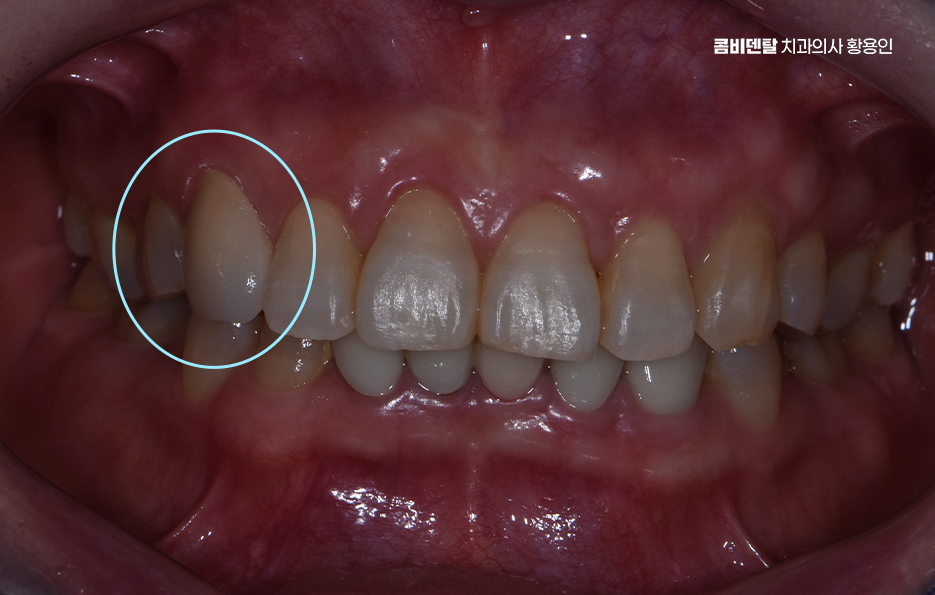

특히 송곳니 크라운 치료가 필요한 상황이라면, 단순히 기능 회복만 생각할 게 아니라 모양과 색감까지 자연스럽게 복원하는 게 중요하겠고 이런 경우에 적합한 방법이 바로 올세라믹이나 지르코니아 크라운을 이용한 심미적인 치료라고 할 수 있어요

크라운 치료는 치아가 많이 손상됐을 때, 또는 신경치료 후 치아가 약해졌을 때 치아를 보호하고 형태를 회복시키기 위한 보철 치료인데 쉽게 말하면 보통 씌우기 치료라고 말하는 치아를 보철물로 전체를 덮는 치료로 송곳니처럼 앞쪽에 위치한 치아는 씌운 게 티 나지 않게 만들어야 하니까 재료 선택이 중요하다는 점에서도 올세라믹과 지르코니아 같은 재료가 주로 활용되고 있었어요

올세라믹 크라운은 말 그대로 금속이 전혀 들어가지 않은 세라믹 재료로 만들어진 크라운으로 금속 없이 순수한 도자기로만 제작되기 때문에 빛 투과성이 자연치아와 거의 비슷하고, 치아 본연의 반투명한 느낌을 재현할 수 있으며 특히 송곳니처럼 햇빛이나 형광등 아래에서 드러나기 쉬운 치아는 빛에 반응하는 느낌이 중요한데 올세라믹은 이런 부분에서 우수한 심미성을 보여주는 재료로 말할 때나 웃을 때 자연스럽게 어우러져서 보철물이 있다는 걸 거의 눈치챌 수 없게 만들어줄 수 있을 정도로 송곳니 크라운 재료에서 심미적인 장점이 있어요

송곳니 크라운 치료 시에 자연스러운 결과를 위해 고려해야 할 점으로 또 하나는 잇몸과의 조화로 예를 들어 금속이 들어간 PFM과 같은 보철물은 시간이 지나면서 잇몸 경계에 어둡게 변색되는 현상이 생길 수 있지만 올세라믹은 전혀 금속이 없기 때문에 이런 문제가 없고, 인체 친화적인 소재라 잇몸 자극도 거의 없으며 송곳니는 입술과 접촉이 많은 위치라서 잇몸이 예민한 편인데 올세라믹은 이런 잇몸과도 안정적인 조화를 이루기 때문에 오랜 시간이 지나도 건강한 상태를 유지할 수 있다는 점에서 장점이 있어요